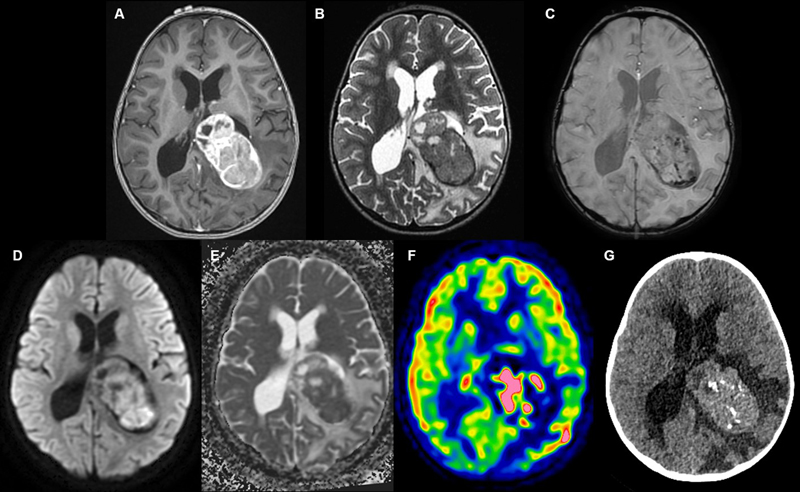

A three-year-old girl, whose sister had Ewing sarcoma, presented with signs of intracranial hypertension. Magnetic resonance imaging (MRI) revealed the presence of a large tumor located in the posterior part of the left lateral ventricle. Cranial computed tomography (CT) scans revealed heterogeneous enhancement and intracranial calcifications (Figure 1A–G). CT scan of the chest, abdomen, and pelvis did not find other abnormalities. Germ cell markers were negative in the blood and in the cerebrospinal fluid. Gross total resection was achieved. Histopathologically, the tumor was pleomorphic with epithelial (arranged in solid sheets and papillary structures), mesenchymal (fascicles of spindle cells in a myxoid stroma and osteoid formation), and melanocytic elements (Figure 2A–D). There was no myogenic differentiation. The cellular density was high, with nuclear pleomorphism, necrosis, and frequent mitotic figures (> 20/2.3 mm2). Using immunohistochemistry, tumor cells were found to variably expressed cytokeratins AE1/AE3, CK18 (Figure 2E), GFAP, PS100, MITF, HMB45 (Figure 2F), desmin and smooth muscle actin. SMARCB1/INI1 (Figure 2G), BRG1/SMARCA4 (Figure 2H) and H3K27me3 expressions were maintained. There was no immunoreactivity for LIN28A, OLIG2, EMA, SALL4, myogenin, NUT, ETV4, BCOR or germinal markers (OCT3/4, PLAP, beta-HCG, and alpha-fetoprotein). There was no expression of p53, and Ki67/MIB1 was expressed in 70 % of cells (Figure 2I). Next-generation sequencing analyses of tumor cells evidenced a homozygous deletion of 3p21.1, including the BAP1 gene and a loss of function TP53 mutation (p.Y220C). RNA-sequencing analysis did not identify any fusion transcript. DNA-methylation profiling analysis classified the tumor as a CPC, pediatric subtype (calibrated scores > 0.9 in both classifiers DKFZ v12.8 and Bethesda NIH v2.0). Using t-Distributed Stochastic Neighbor Embedding analysis, the tumor clustered with a case previously reported (3), in close vicinity to CPC, pediatric subtype (Figure 3A–C). Whole exome sequencing analysis failed to reveal a BAP1 or TP53 germline alteration. Considering all these results, a complementary immunostaining of BAP1 was performed and evidenced a loss of protein expression in tumor cells (Figure 3B). The patient received conventional and high-dose chemotherapy, followed by local radiation therapy. One year post treatment, a distant recurrence in the anterior right lateral ventricle was detected on imaging and confirmed by repeat resection. Histopathology was consistent with the initial tumor. At present, 21 months after the initial diagnosis, the patient is alive.

Figure 1. Radiological features.

A. An intraventricular mass in contact with the choroid plexus showing heterogeneous enhancement after injection of gadolinium on T1-weighted computed tomography (CT) images. B. Intermediate T2 signal. C Calcifications and hemorrhagic changes on susceptibility weighted imaging. D–E. Diffusion restriction and low apparent diffusion coefficient. F. Elevated perfusion on arterial spin labeling perfusion imaging. G. CT scans showing intracranial calcifications.